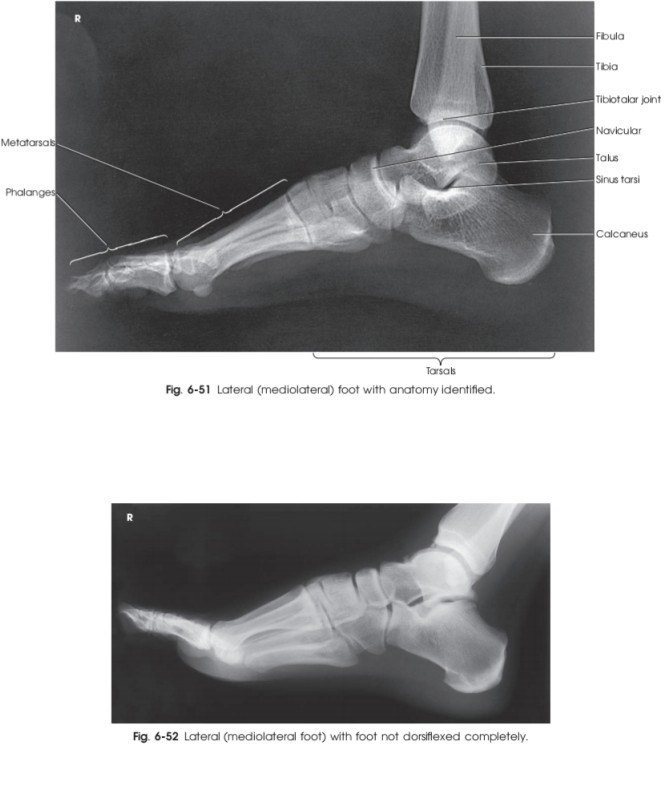

عکس رادیولوژی از مچ پای سالم